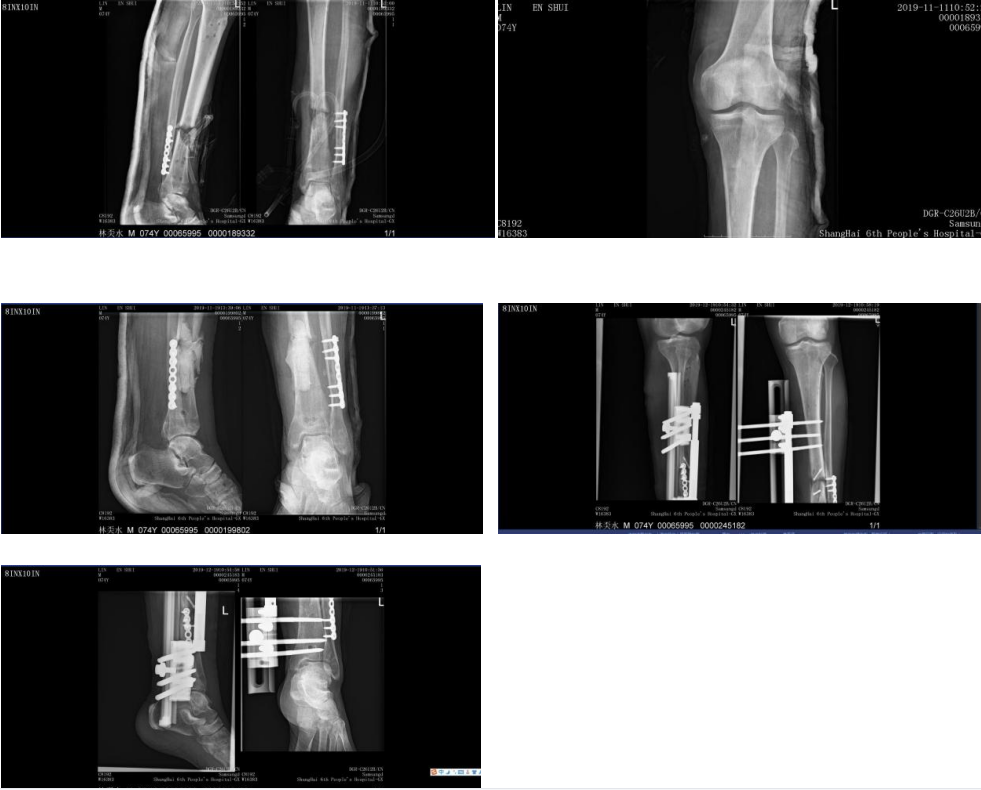

林先生在8个月前在当地医院进行手术治疗。术后3个月,行X片检查,考虑左胫骨骨不连,行髂骨植骨术,术后出现左下肢下段肿胀,表皮隆起,继续抗炎治疗。久治不愈,最终选择上海市第六人民医院骨科求诊。

确定手术方案后,在与患者详细沟通及医护人员的精心准备下,医疗团队行左胫骨清创VSD+内固定去除术。术后5天创面炎症控制后,再行清创骨水泥填塞术。6周后,创面愈合,血常规、血沉、白介素等检查指标正常后行骨水泥去除+植骨+外支架固定术。术后骨折完全愈合。

文根主任指出林先生久治不愈的重要原因在于感染,包括当地医院考虑的骨不连,均与感染有关。因此,彻底清创是治疗感染的基础,也是后续手术顺利进行的前提。除此之外,针对骨髓炎,还需要利用外科手术完成骨与软组织的重建。经过文根主任团队详细讨论后,决定采用“Masquelet技术”,即“骨诱导膜技术”进行治疗。该技术具有并发症少、骨愈合快、愈合率高等优点。